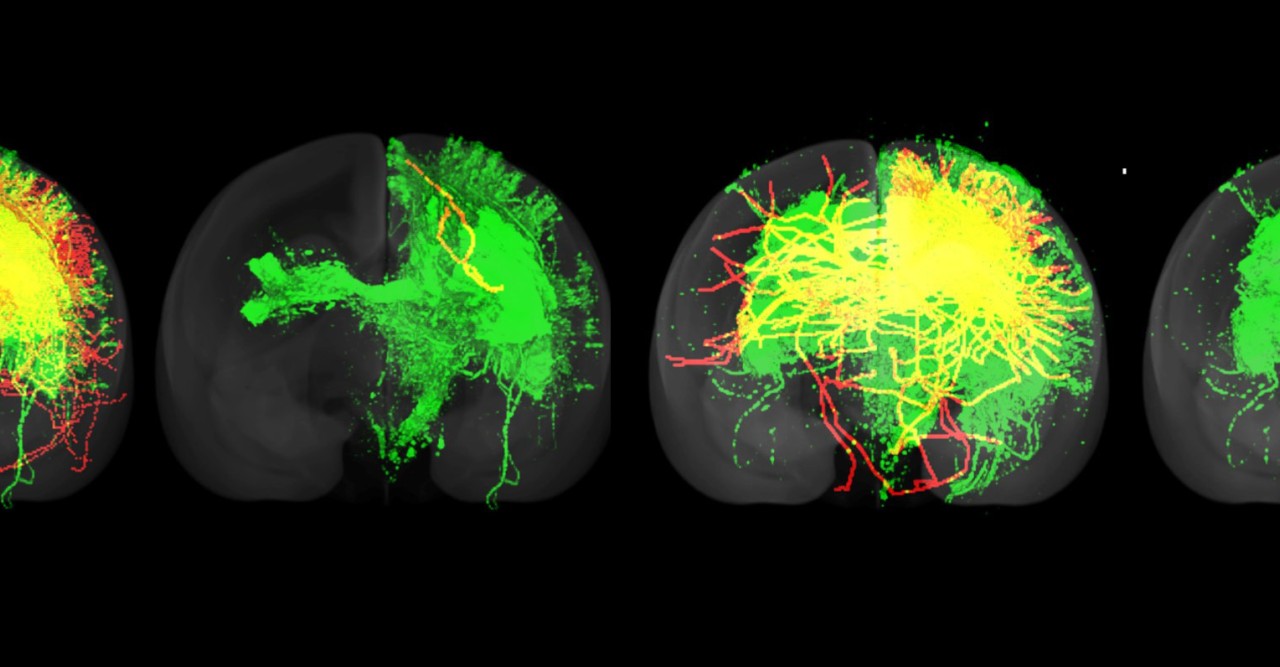

The green represents nerve fibers detected by injecting a fluorescent tracer at a single point. The red represents nerve fibers detected using a diffusion MRI-based fiber tracking algorithm. Only the nerve fibers that also connected up to the point where the tracer was injected are shown. The yellow represents nerve fibers that were detected using both techniques. The results show that the optimized algorithm performed better than the default algorithm, not only on a brain it was trained on, but on a previously unseen brain. The optimized algorithm detected a higher number of fibers and also fibers that stretched longer distances.

The striking difference between the images constructed by algorithms using the default and optimized parameters sends out a stark warning about MRI-based connectome research, the researchers said.

“It calls into question any research using algorithms that have not been optimized or validated,” cautioned Dr. Gutierrez.